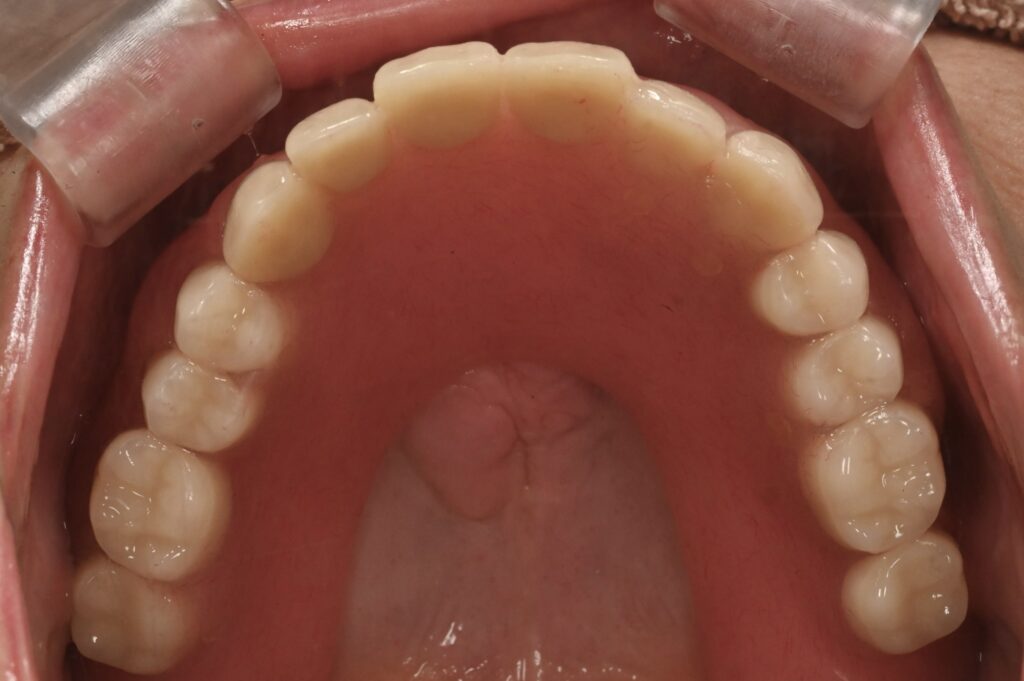

歯を失ってしまった場合の治療方法には ブリッジ、入れ歯、インプラントが考えられます。 口の中の状況、残っている歯の本数、費用などにより、どの治療が1番適しているかが変わってきます。 特に複数本の歯を失っている場合、ブリッジが適用できない場合があります。 その際に選択できるのが、入れ歯かインプラントになります。 インプラントはしっかり噛むためにとても良い治療方法だと考えますが、 金額がかかってしまう 外科処置が必要なため全身状態が不良な人にはリスクがある 治療期間がかかる などのデメリットがあります。 そういったことを考慮して入れ歯を選ぶ患者さんもいらっしゃいます。 今回は入れ歯の相談で来院された患者さんです。 元々、入れ歯を使用していたが、歯にかける金具が見えるのが気になるとの事です。 治療前の口腔内写真です。 下の歯は2本のみ残存しており、その部分に入れ歯をかけている状態でした。 正面から口元を見ると、歯にかけている入れ歯の金具があるのが分かります。 今回は歯の本数が少ないため、ブリッジを選択することができないのと、治療期間、金額の面を考慮し目立たない入れ歯を検討することになりました。 通常、保険の入れ歯では金具を使用する必要があります。 そのため、金属を使用しない保険外の入れ歯、ノンクラスプデンチャーをおすすめしました。 ノンクラスプデンチャーとは歯茎の色に近い特殊な樹脂を使用します。 利点 柔軟性があり、フィット感が高いため違和感が少なくなる。 入れ歯が歯を包み込む設計のため、周囲の歯に負担をかけづらい。 入れ歯の下に食べ物などの汚れが入りづらい。 金属を使用しないため、金属アレルギーの心配がない。 審美的である。 欠点 保険外治療のため費用がかかる。 歯の状況によって適用できない場合がある。 同意を得て、治療に移ります。 保険外専用の材料を用い、精密な型取りを行います。 そして歯と歯茎の形に合わせた入れ歯を作成していきます。 ケースにもよりますが、 型取り→咬み合わせの記録採取→試適→完成といった流れで進みます。 4−5回の来院が必要になることが多いです。 完成し装着した状態の口腔内写真です。 口元の写真です。 金具を使っていないため、入れ歯を装着しているのが外から見ても分かりづらいと思います。 審美面のみではなく、入れ歯の下に食べ物が入りづらく、硬いものもよく噛めると患者さんに大変喜んで頂けました。 患者さんのお口の状態によって、ブリッジ、インプラント、入れ歯の中で1番適した治療方法は異なると考えています。 一人一人の患者さんとしっかりとお話しをした上で治療方法を検討していきます。 お気軽にご相談ください。 よくある質問 ここで患者さんからよくある質問を挙げたいと思います。 Q:入れ歯はすぐ作れますか? A:残っている歯の状態が問題なければすぐに型取りを行い、作成可能です。ただし、治療が必要な歯があれば、まずその歯の治療を行った上で型取りをする必要があります。 Q:痛みが出ますか? A:新しい入れ歯を装着する際には歯茎に当たって痛い場合があります。また、長期的に使用していくと歯茎の形も変化してくるため痛みが出ることもあります。その際は入れ歯の調整をすれば痛みを取り除くことが可能です。 Q:メリット、デメリットを教えてくだい。 A:メリット:周囲の歯を削らない。治療期間が短く済む場合がある。 デメリット:違和感がある。噛む力があまり発揮できない。材料にもよるが審美面に影響が出ることがある。 治療期間 1ヶ月 治療費 ¥150,000 + tax 治療のリスク 材料が欠けてしまう可能性がある。 長期的に使用すると調整が必要な場合がある。